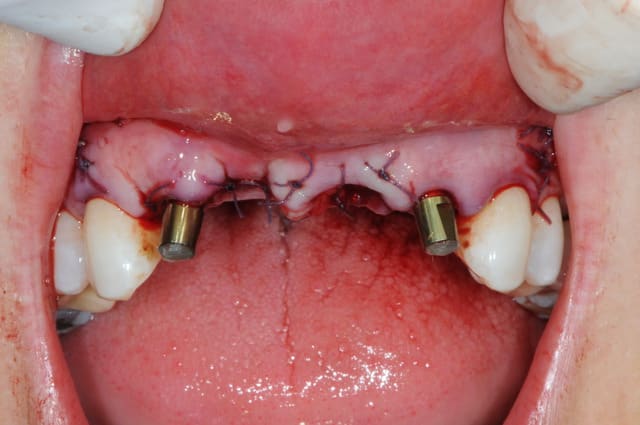

la chir...

extraction de 12 et 22 pour commencer et pour connaitre la limite maxi d'implantation dans la crête osseuse.

grosse déception quant à la table externe au niveau de 11

pour les axes, j'avoue que je me suis fait avoir comme une bleusaille (mais bon, j'en suis une), je me suis un peu laisser embarquer par l'axe des alvéoles. c'est dure l'implanto.